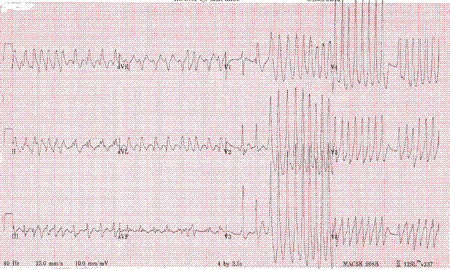

Atrial fibrillation with Wolff-Parkinson-White syndrome

From the collections of Arti N. Shah and Bharat K. Kantharia